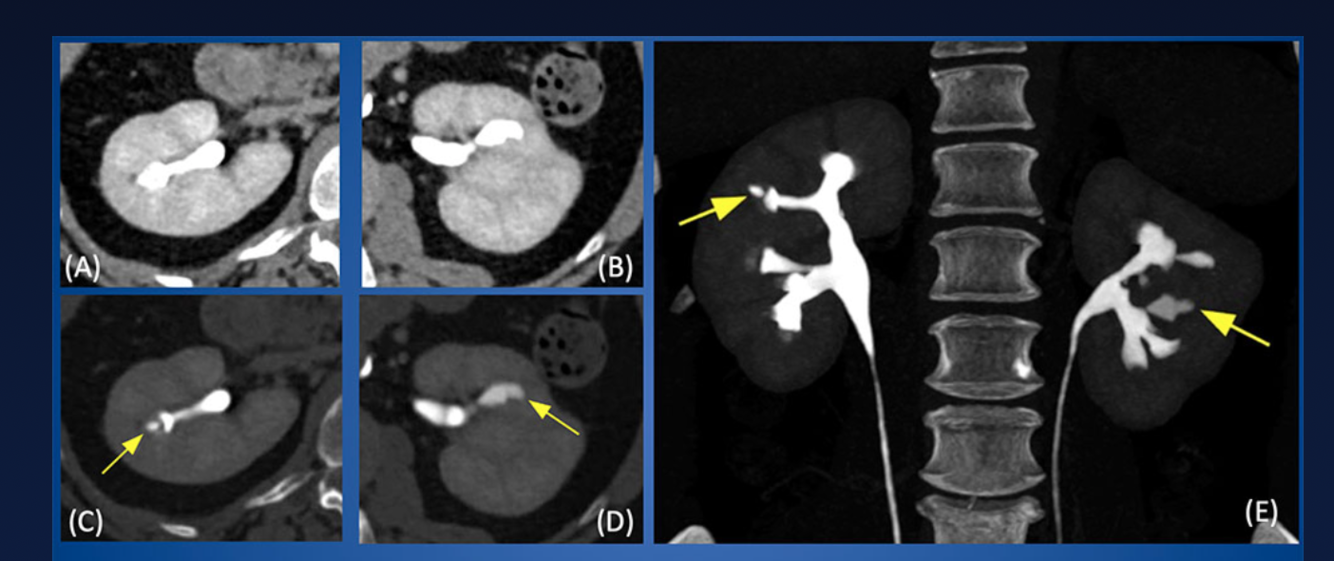

Pyelorenal Backflow

Backflow of contrast material from collecting system into renal or perirenal spaces. Usually caused by increased pressure in collecting system from retrograde pyelography or ureteral obstruction.

(lymphatic type)

https://www.tandfonline.com/doi/pdf/10.3109/00016925309175821